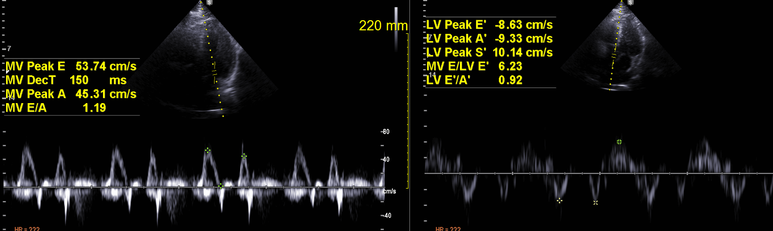

심초음파; 수축기 이완기 기능 정상

판막 역류, 협착 소견 없음

벽운동 감소한 부분 없음

concentric remodeling